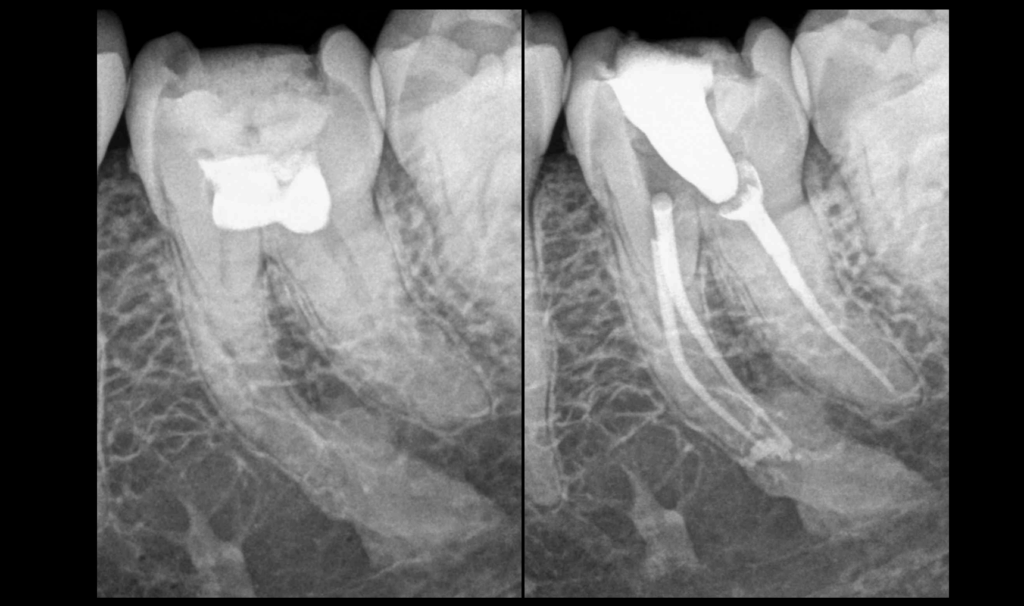

𝐀𝐓𝐂𝐃 𝐝𝐞 𝐩𝐮𝐥𝐩𝐨𝐭𝐨𝐦𝐢𝐞 𝐭𝐨𝐭𝐚𝐥𝐞, 𝐨𝐬𝐭𝐞́𝐢𝐭𝐞 𝐜𝐨𝐧𝐝𝐞𝐧𝐬𝐚𝐧𝐭𝐞

📌 L’𝐨𝐬𝐭𝐞́𝐢𝐭𝐞 𝐜𝐨𝐧𝐝𝐞𝐧𝐬𝐚𝐧𝐭𝐞 résulte d’une 𝐩𝐮𝐥𝐩𝐢𝐭𝐞 𝐜𝐡𝐫𝐨𝐧𝐢𝐪𝐮𝐞.

🔥 L’𝐢𝐧𝐟𝐥𝐚𝐦𝐦𝐚𝐭𝐢𝐨𝐧 𝐩𝐮𝐥𝐩𝐚𝐢𝐫𝐞 𝐫𝐚𝐝𝐢𝐜𝐮𝐥𝐚𝐢𝐫𝐞 entraîne non pas une 𝐫𝐚𝐫𝐞́𝐟𝐚𝐜𝐭𝐢𝐨𝐧 𝐨𝐬𝐬𝐞𝐮𝐬𝐞 (comme la lésion apicale) mais une 𝐡𝐲𝐩𝐞𝐫𝐝𝐞𝐧𝐬𝐢𝐟𝐢𝐜𝐚𝐭𝐢𝐨𝐧 𝐨𝐬𝐬𝐞𝐮𝐬𝐞.